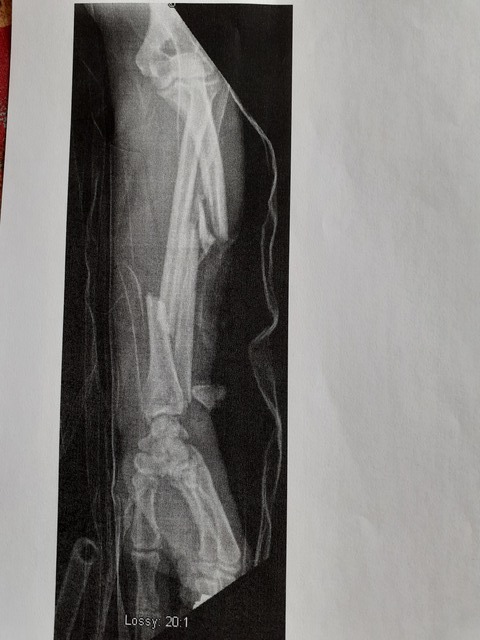

avant bras (se repérer aux bagues en bas)

Image

Pour le cliché radio de ta jambe, putain, j'étais au café-tartine du matin :lol:

désolé pour la tartine, -d'ailleurs j'ai peut-etre oublié de preciser que la 1ere radio c'est le genou, et la 2eme le bras^^